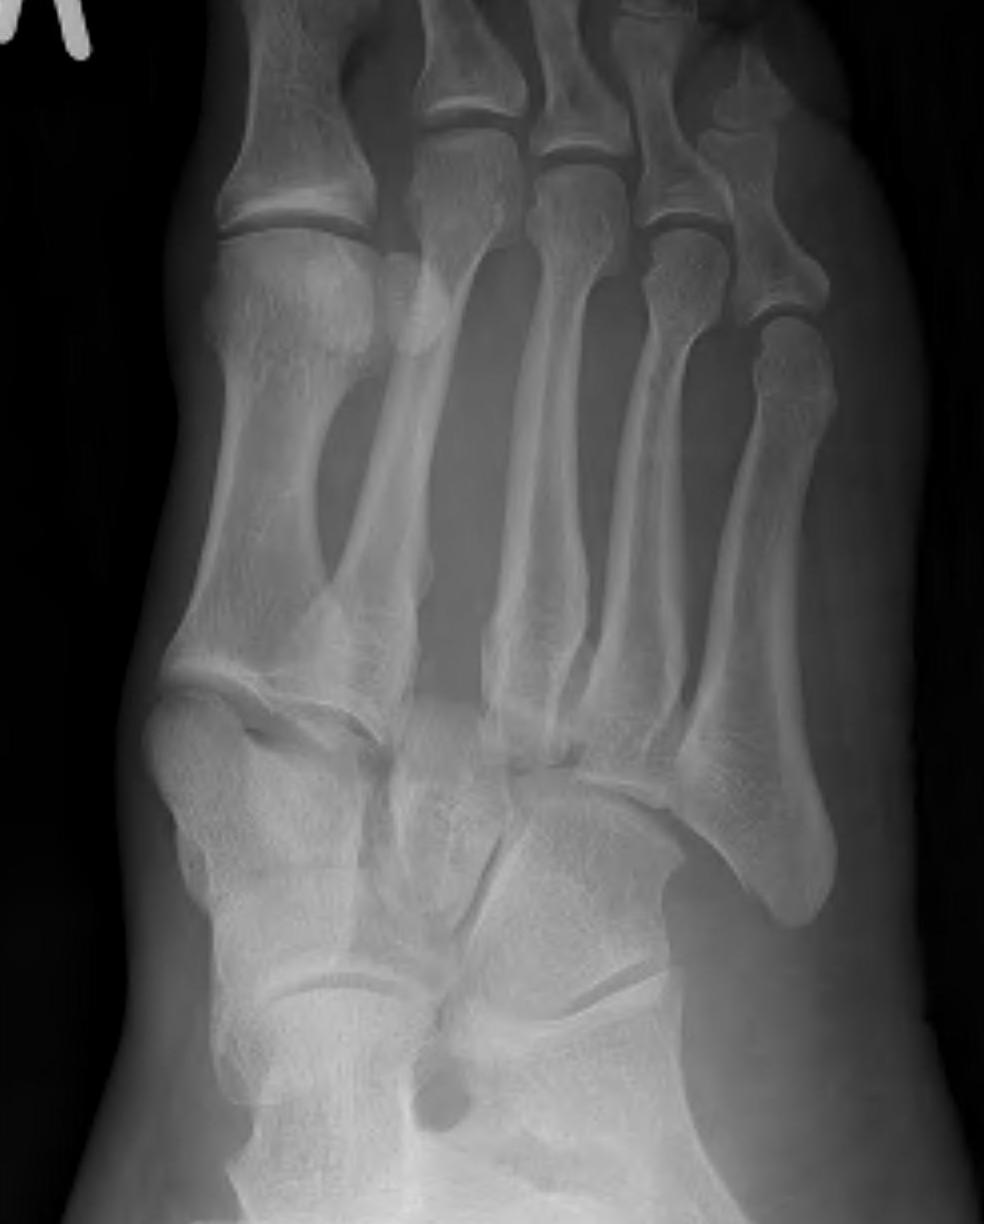

Imaging

1. Diastasis of the intermetatarsal gap between the 1st and 2nd metatarsals

2. Widening of the space between the medial cuneiform and base of 2nd metatarsal

3. Second metatarsal Fleck sign - avulsion of Lisfranc ligament from base of 2nd metatarsal

4. Widening of inter-cuneiform distance

5. Dorsal subluxation of the metatarsals

6. Tarsometatarsal alignment disruption

- medial border 1st metatarsal aligns with medial border medial cuneirform (AP foot)

- medial border 2nd metatarsal aligns with medial border middle cuneiform (AP foot)

- medial border 3rd metatarsal aligns with medial border lateral cuneiform (AP view)

- medial border 4th metatarsal aligns with medial border of the cuboid (oblique view)

X-ray

AP / Assess medial column

Internal Oblique 30o / Assess lateral column

Lateral / assess dorsal displacement